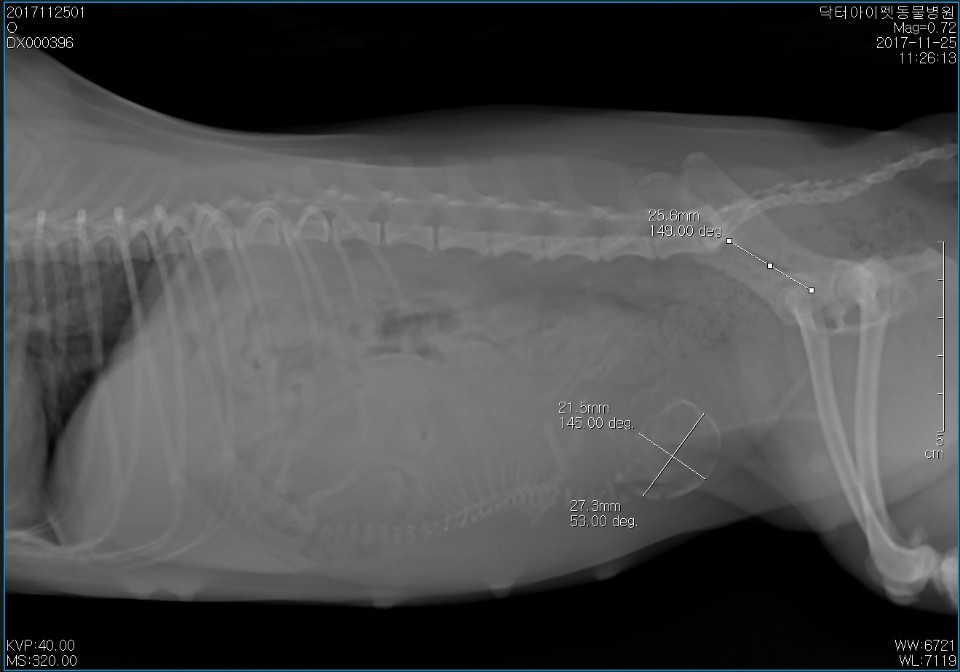

거대태아를 임신한 꼬마의 방사선 사진

안 좋았다. 거대태아였다. 한 마리만 임신된 상태였다. 이 아이가 혼자 너무 많은 양분을 흡수하여 자연분만이 불가능할 정도로 뱃속에서 커버렸다. 이럴 경우에는 제왕절개술(C-sac)을 해야 한다.